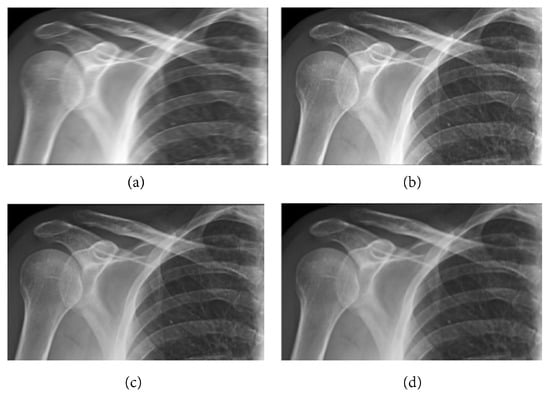

The following numerical results are proposed: Figure 2 presents the original grayscale images for (a) X-ray film of the brain and (b) X-ray film of the right shoulder. Figure 3 and Figure 6 are blurred X-ray films of the brain and the right shoulder images with filtering M i x in the part of degradation of Figure 1. In this example, we set N = 4 . So, we have M 1 x , M 2 x , M 3 x , and M 4 x . Figure 4a, X-ray films of the brain and the right shoulder images were obtained via Theorem 2. Figure 4b, X-ray films of the brain and the right shoulder images were obtained via Theorem 3.1 in [16] (Khuangsatung and Kangtunyakarn’s method). Figure 9 is an X-ray film of the brain image that was recovered via the proposed method that was tuned for the parameter λ.

Figure 6. Blurred X-ray film of the right shoulder image with filtering M i x by (a) M 1 x , (b) M 2 x , (c) M 3 x and (d) M 4 x .